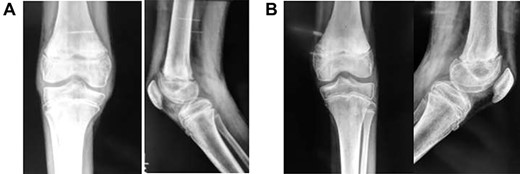

A 9-year-old male presented to the ER within 6 h of injury to both knees, with swelling, restricted movements and tenderness bilaterally. Assessment demonstrated distal pulses in both legs. Initial management was with pain relief—neurological status was not assessed due to pain. A history of direct fall of a concrete block onto both knees whilst sitting with legs extended and raised on a stool at a building site, leading to a forced hyperextension injury, was elicited. The patient received no treatment before presenting to our unit. Radiography suggested bilateral completely displaced Salter-Harris Type I fractures (Fig 1A–C). All routine laboratory and metabolic profiles performed were within normal ranges. Patient was transferred to theatre immediately after radiography for a closed reduction.

(A) Lateral view of right knee at presentation, (B) lateral view of left knee at presentation, (C) frontal view of both knees at presentation